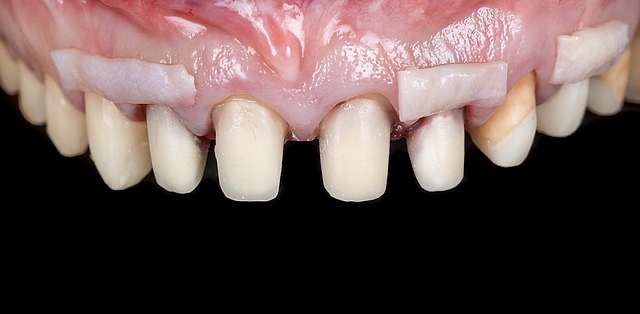

Grefa gingivala este o micro-chirurgie prin care se transplanteaza o mica bucata de tesut moale - gingie sau tesut conjuctiv (stratul intern al gingiei) pentru a acoperi un defect gingival. De obicei, acest tip de interventie este necesar pentru augmentarea implanturilor dentare, sau pentru a acoperi defecte cauzate de traume sau de afectiuni parodontale.Grefele se recolteaza din zona molarului de minte, sau de pe palat, si sunt transplantate in zona afectata.

Grefe pentru corectia nivelului si a retractiei gingivale